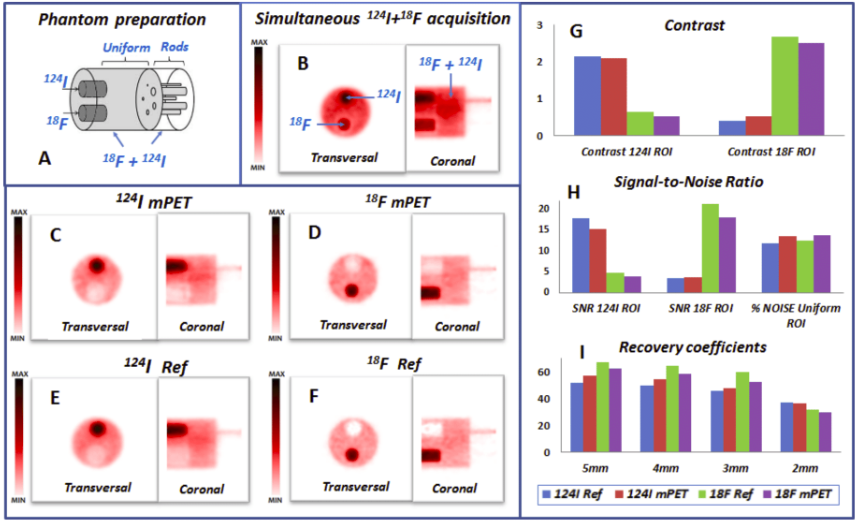

| ABSTRACT | Introduction: Simultaneous in-vivo imaging of several biological processes may improve oncological, neurological and cardiovascular studies by providing complementary information obtained under the same exact conditions and coregistered in space and time. Standard PET imaging does not allow multiplexed acquisitions, as all annihilation photons have the same energy. We developed a technique called multiplexed PET (mPET), which uses a tracer labelled with a pure positron emitter (such as 18 F, 13 N, 11 C), and a tracer labeled with a positrongamma emitter (such as 124 I, 76 Br, 82 Rb, 86 Y). Positrongamma emitters generate a significant number of triplecoincidences , which allows them to be differentiated from the standard PET radionuclides . In this work, we evaluated the performance of mPET using phantom and animal experiments. |